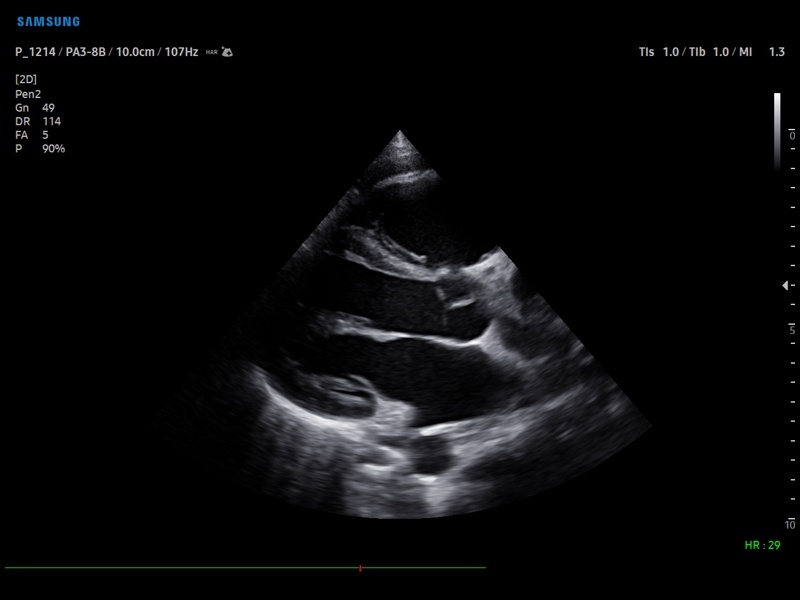

• Кардиология

• M - одномерный режим для исследования сердца, анатомический М-режим (необходим кардиопакет), CM - цветной М-режим (необходим кардиопакет).

• Кардиопакет: тканевый допплер (TDI) + анатомический М-режим + цветной М-режим (CM) + программное обеспечение.

• Пакет кардиологических исследований.

М-режим:измерение диаметра аорты, передне-заднего размера ЛП, толщины МЖП (систолическая и диастолическая), толщины ЗСЛЖ (систолическая и диастолическая), размеров ЛЖ и ПЖ (систолический и диастолический), ФВ (Teichholz).

B-режим:измерение диаметра аорты (восходящей, дуги, нисходящей, на уровне синусов Вальсальвы, на уровне створок аортального клапана), определение размеров ЛП и ПП (максимальный, минимальный, систолический, диастолический, переднее-задний, верхнее-нижний, медиально-латеральный), расчет объемов ЛП и ПП, объемов ЛЖ (метод "Площадь-Длина", метод дисков (Simpson)), массы миокарда ЛЖ, индекса массы миокарда ЛЖ.

• Модуль Stress Echo – программа для исследования сердца под нагрузкой.